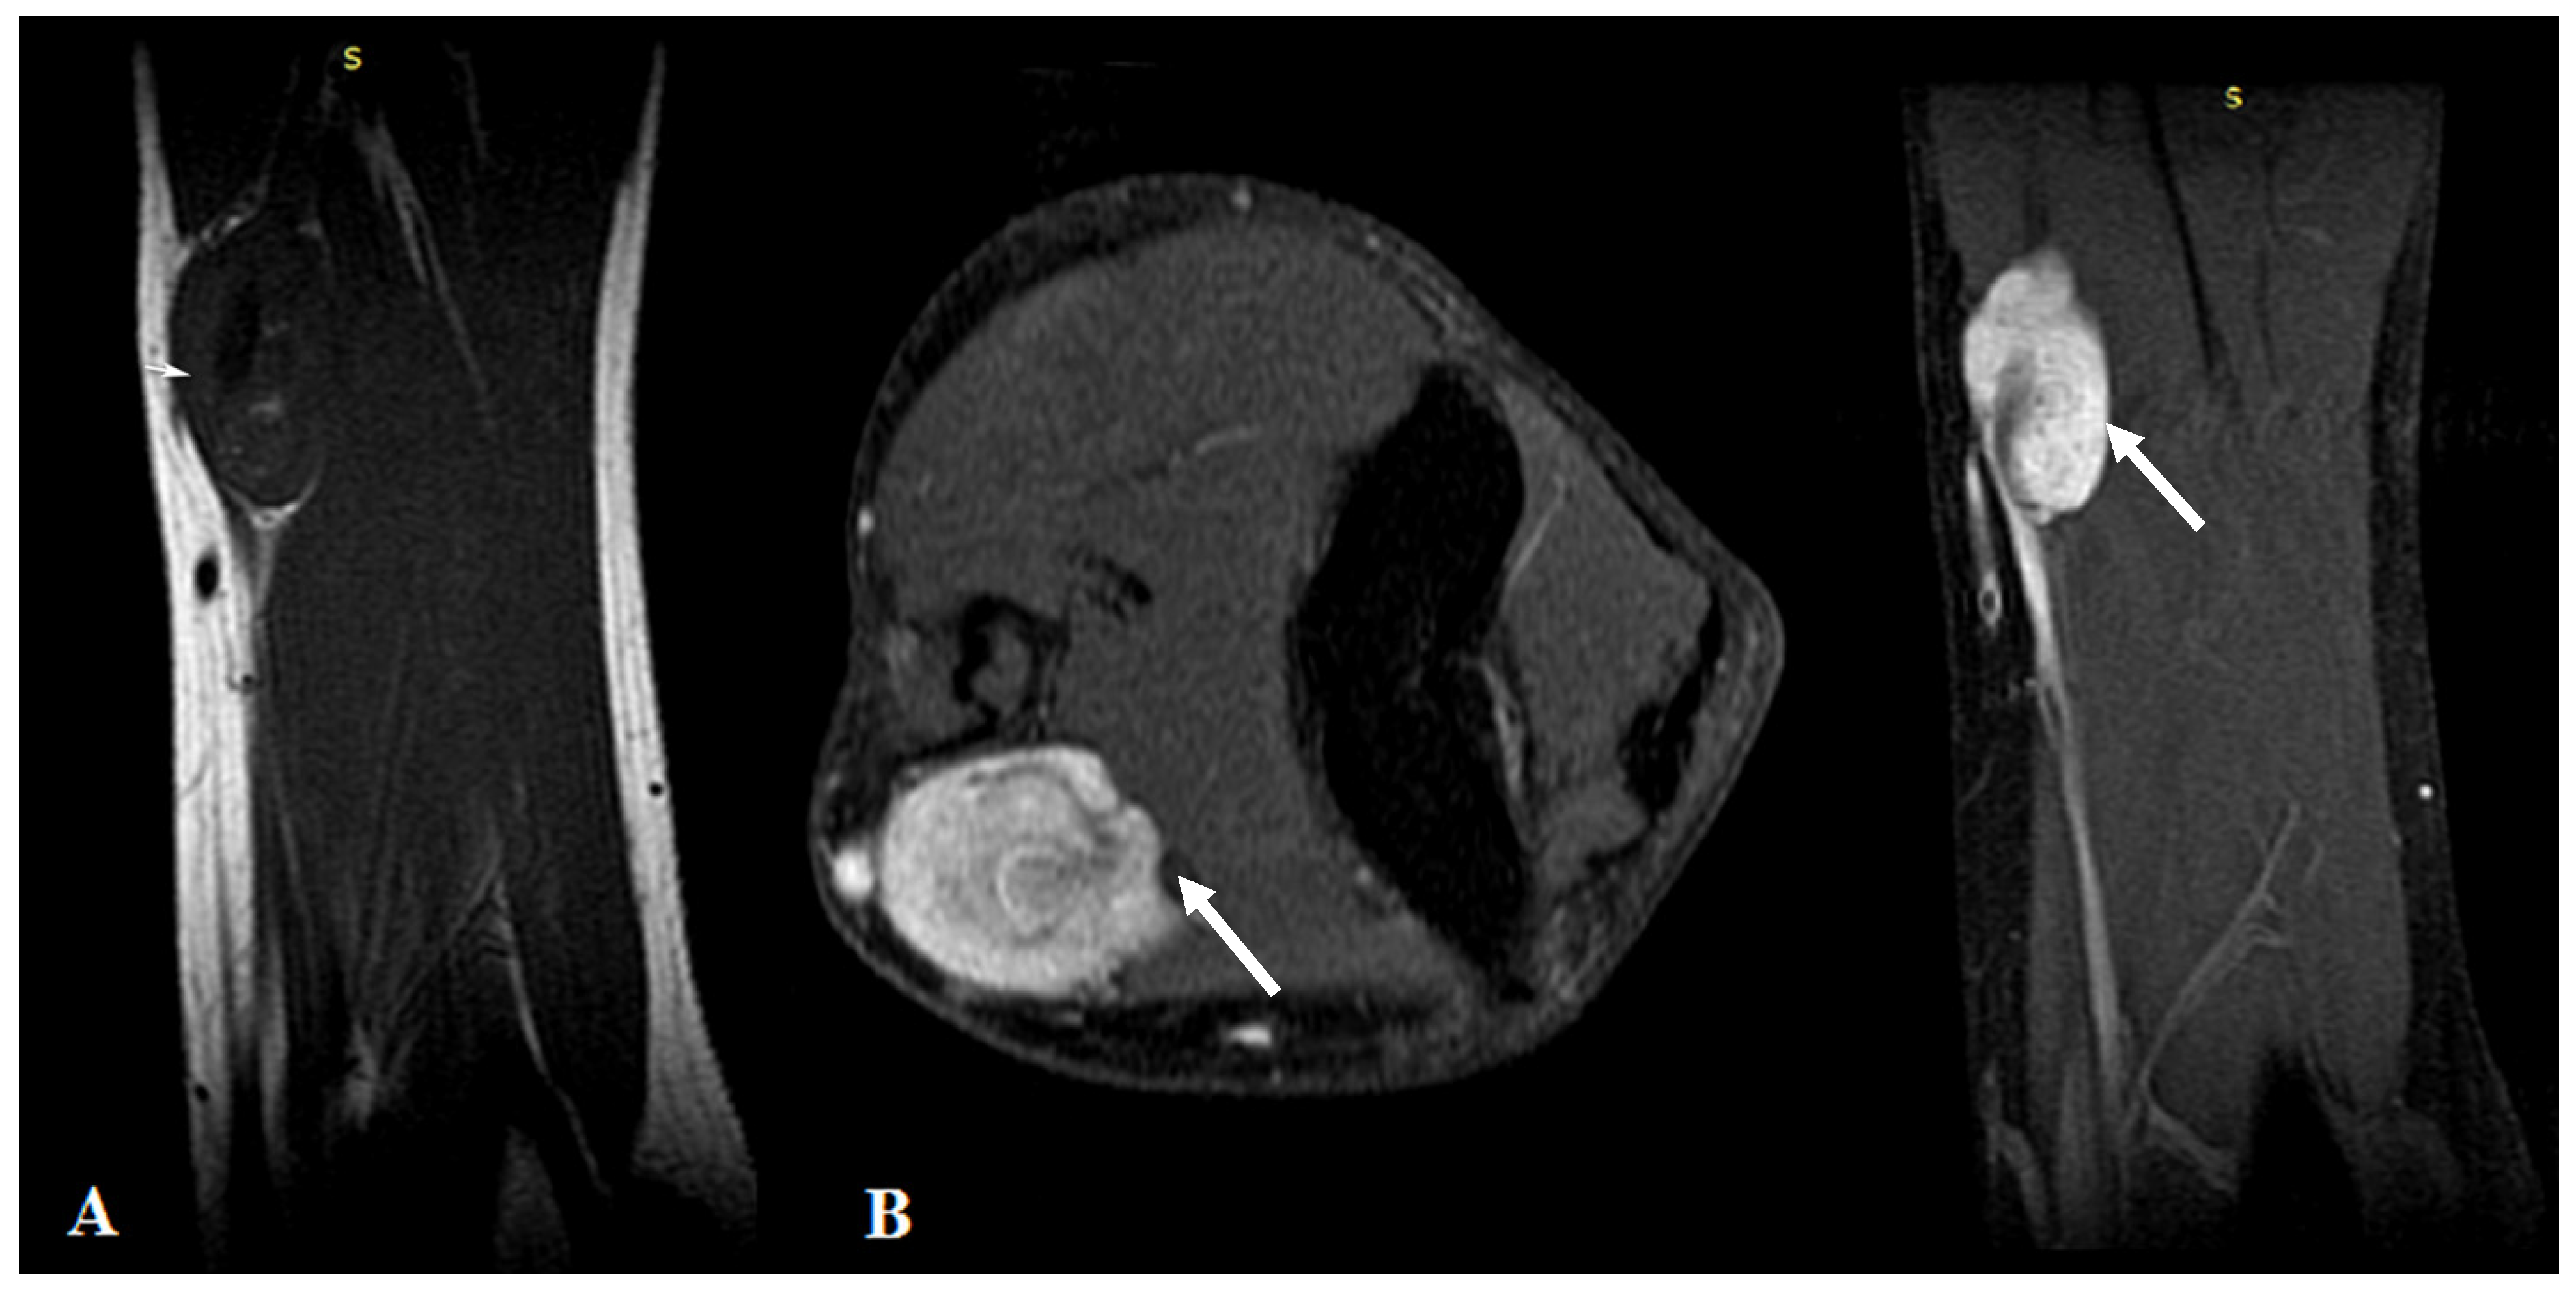

| Manole et al./2022 | US | First-line imaging tool |

| - detection and characterization | ||

| - assessment of the vessel | ||

| - follow-up | ||

| MRI | Second-line imaging tool | |

| - boundaries and relation with surrounding structures | ||

| - +/−invading features | ||

| - soft tissue edema | ||

| - distant metastasis |